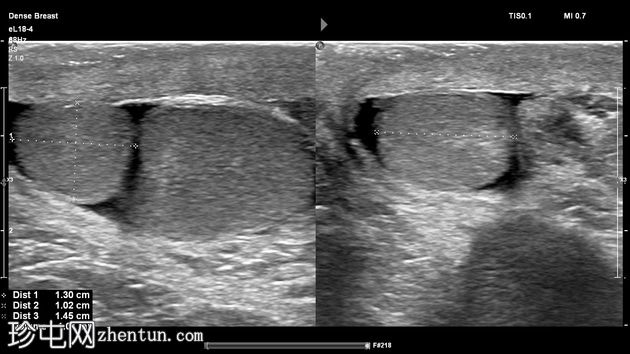

左侧阴囊内可见两个相邻但彼此分离的小睾丸,头侧体积分别为1毫升和3.5毫升,共用一个附睾。

两个睾丸回声和血流均正常,内部未见病变,但患侧可见少量鞘膜积液。